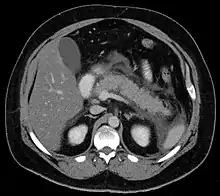

Calcified pancreatic duct stones with some free intra-abdominal fluid

A contrast-enhanced CT scan is usually performed more than 48 hours after the onset of pain to evaluate for pancreatic necrosis and extrapancreatic fluid as well as predict the severity of the disease. CT scanning earlier can be falsely reassuring.